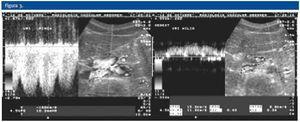

La ecografía Doppler, al igual que la TC realizada, demostró la compresión de la vena renal izquierda entre la arteria mesentérica superior (AMS) y la aorta abdominal (A). En la ecografía Doppler se demostraba un efecto de pinza sobre la vena renal principal izquierda (VRI) que se traducía en una asimetría de flujo venoso entre ambos riñones, siendo de amplitud y pulsatibilidad disminuída en el lado izquierdo. Se observaba también circulación colateral retroaórtica (CCR) con inversión de flujo en la vena ovárica izquierda. En la TC se evidenciaba circulación colateral retroaórtica (vena renal retroaórtica accesoria).

Figura 2.